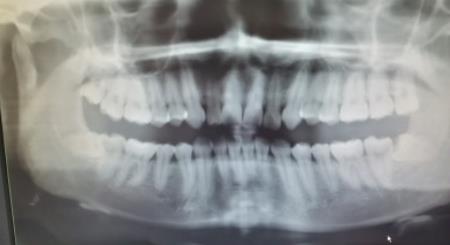

拔牙就像拔蘿卜一樣,牙齒拔出後在對應位置會(hui) 有一個(ge) 坑,也叫拔牙窩。拔牙窩內(nei) 剛開始會(hui) 出血,需要壓棉球半個(ge) 小時左右止血,而且24小時內(nei) 不要刷牙漱口,等血凝塊形成,周圍軟組織長好,拔牙窩才會(hui) 慢慢長平。

因此,為(wei) 了不破壞血凝塊,造成感染,影響拔牙後恢複,通常醫生是不建議在一兩(liang) 周內(nei) 再拔智齒的。

不過具體(ti) 還是要看個(ge) 人的恢複能力,比如有的年輕人,可能一周後就恢複得差不多了,而年齡較大的人需要的時間稍微長一些,要兩(liang) 周左右。

拔牙後間隔多長時間,在醫生指導下,滿足條件的情況,**可以自行安排時間。比如有的**會(hui) 選擇在拔牙後一個(ge) 月或三個(ge) 月,而有的患會(hui) 者選擇半年甚至一年後再次拔牙。這通常都是可以的。

對於(yu) 間隔的時間,大家不需要過於(yu) 心急。建議聽從(cong) 醫生建議比較好。畢竟拔牙也是一個(ge) 小手術,而且智齒拔牙比較複雜,張嘴時間長,可能會(hui) 造成下頜關(guan) 節不適,需要一些時間恢複。

其實重要的一個(ge) 原因是,拔牙後會(hui) 影響進食,如果拔除兩(liang) 側(ce) 的智齒,需要分開進行,等到拔牙側(ce) 可以開始吃東(dong) 西了,再進行另一側(ce) 的拔牙比較好,如此一來,左右側(ce) 交替拔牙不會(hui) 影響進食。